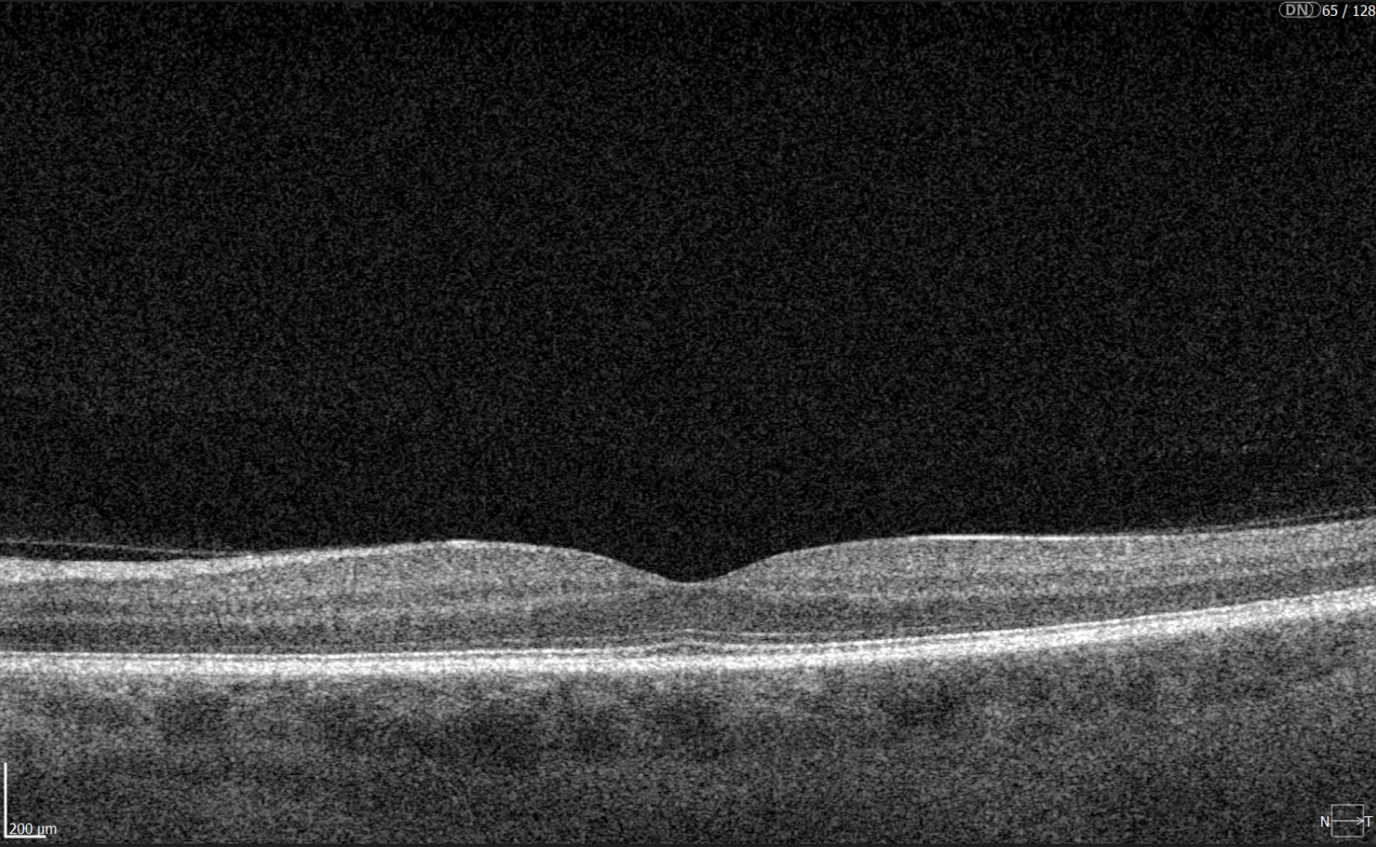

New Tech in Optometry: New Iterations of OCT

Even though OCTs entered the market relatively recently, they swiftly became indispensable ancillary tests in ophthalmic practice for many professionals. The primary reason is their high-quality imaging of the retina, nerve fiber layer, and optic nerve, offering a near in-vivo “optical biopsy” of the retina.

However, the technology continues to evolve – partly due to technological advancements and partly due to the ability to extract even more data from OCT machines through sophisticated software.

En-face OCT in current systems is based on software reconstruction of OCT images. Image slices are selected retrospectively from full recorded volumes or calculated by depth projection along specific depth ranges, enabling three-dimensional data visualization in a fundus projection. This technique allows the projection of specific retinal and/or choroidal layers at a given depth onto an en-face view.

While we are more accustomed to working with cross-sectional images (B-scans), microstructural changes and the retinal and choroidal vasculature morphology are challenging to evaluate using B-scans alone. En-face OCT offers numerous advantages, including the ability to precisely localize lesions within specific subretinal layers using their axial location on OCT cross-sections and to register projected OCT images to other fundus imaging modalities using retinal vessels as landmarks.

Currently, en-face OCT is being applied to various specialized areas within the eye, encompassing the anterior segment, glaucoma, infectious diseases, and the retina.

Optometry Technology: SS-OCT

Like SD-OCT, swept-source OCT (SS-OCT) utilizes Fourier domain technology to optimize higher-quality wavelength transduction within the frequency domain. This enables rapid sweeping scan patterns across a broad bandwidth.

However, instead of a broad-bandwidth light source projected all at once, as in SD-OCT, SS-OCT employs a single tunable laser that sweeps through different frequencies to cover the entire spectrum swiftly. The light reflected from the eye is captured by a photodetector significantly faster than the charge-coupled device (CCD) camera used in SD-OCTs. This difference translates to a faster scanning speed of up to 400,000 axial scans per second, eliminating the typical depth-dependent signal drop-off associated with SD-OCT. Additionally, the faster scanning speed reduces image distortions caused by eye movements and allows for wider B-scans, facilitating widefield imaging.

Furthermore, many SS-OCT systems utilize a light source centered at an approximately 1050 nm wavelength, providing better tissue penetration than SD-OCT. This allows for visualization of structures like the choroid, lamina cribrosa, and structures at the anterior chamber angle. This enhanced penetration is crucial in diseases like Central Serous Chorioretinopathy, where evaluating the entire thickness of the choroid can be challenging.

Moreover, volumetric analysis of the choroid and various pathological features can aid in monitoring the progression of Wet AMD, CSCR, and Diabetic Retinopathy, as well as assessing the response to treatments such as anti-VEGF agents, laser photocoagulation, and photodynamic therapy (PDT).